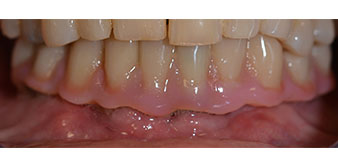

L'empreinte et l'enregistrement de l'occlusion ont ensuite été effectués afin que le prothésiste dentaire puisse commencer à réaliser la restauration provisoire. Celle-ci a été vissée le jour même (Fig. 17 et 18).

Fig. 17

Fig. 18